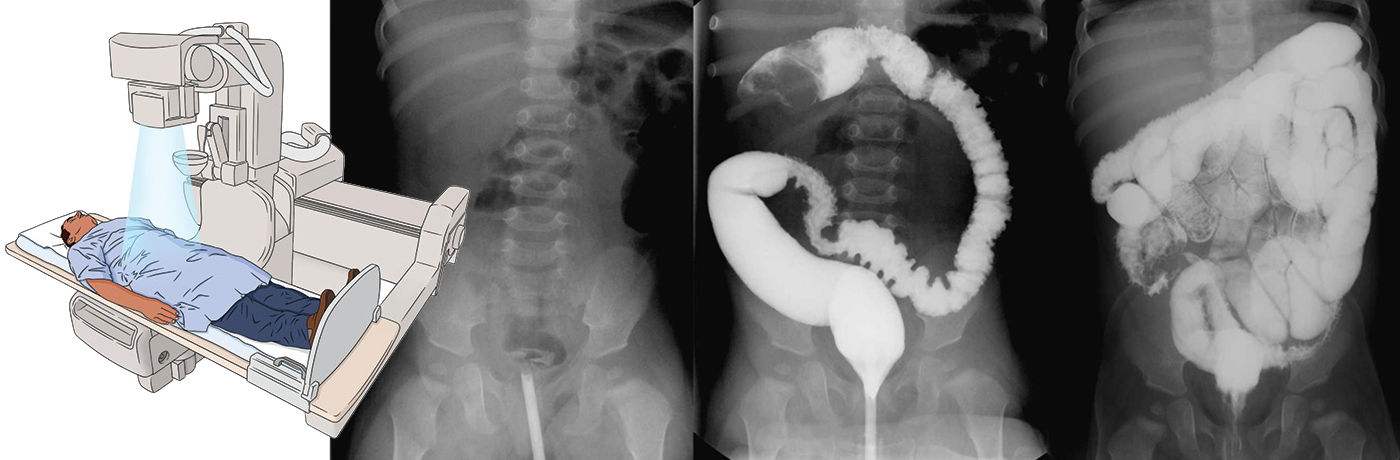

Іригоскопія або іригографія являє собою метод обстеження товстої кишки, який проводиться з використанням рентгенологічного обладнання та контрастування, що вводиться в кишку ректальним способом. Контрастною речовиною виступає суміш води та порошку сульфату барію, який не всмоктується в кишечник, що робить орган гарно видимим під час проведення рентгенографії. Кількість контрастної речовини обчислюється персонально для кожного пацієнта.

Під час проведення іригоскопії, завдяки введеній у кишечник контрастній речовині, лікар у реальному часі оцінює всі можливі зміни кишечника, включаючи слизову оболонку.

У процесі проведення процедури він оцінює стан контурів кишечника, розташування, зміщуваність, наявність та характер патологічних змін.

Проходження контрастної речовини по кишечнику, виділяє його серед інших органів і дозволяє визначити всі відхилення від норми на екрані монітора, фіксуючи їх на рентгенівському знімку.

Барієвий контраст візуалізує всі відділи товстого кишечника, дає уявлення про анатомічні та функціональні особливості роботи органа.